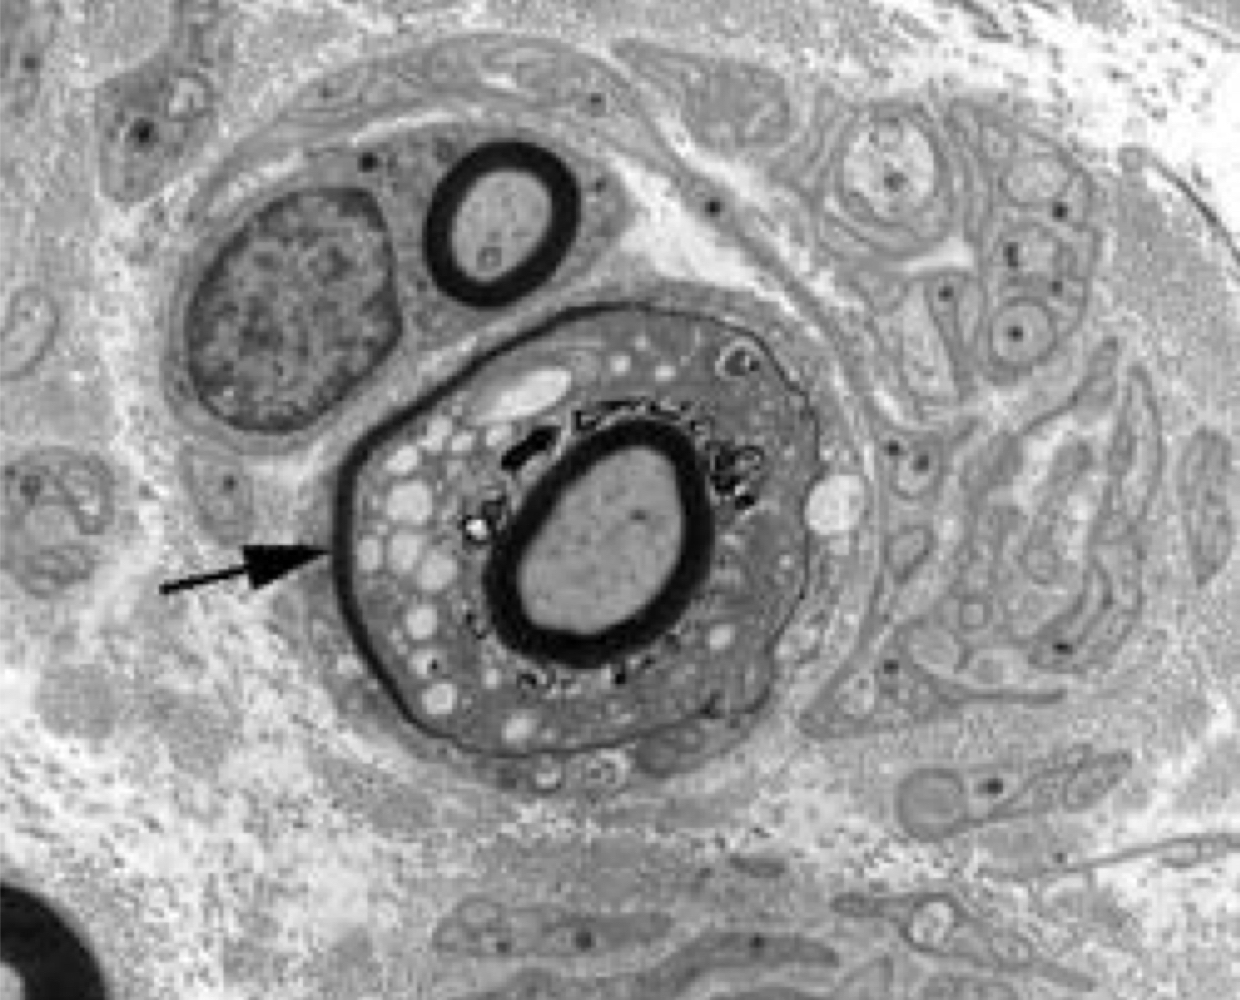

Coonhound paralysis:

demyelination - splitting of myelin lamellae, myelin debris

Coonhound paralysis, demyelinated axon:

myelin debris from myelin breakdown within cytoplasmic processes of macrophages

• naked axon without myelin